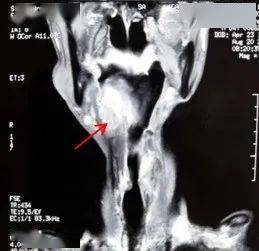

在急诊科完善了相关检查 , 上级医师刘宇此时查看了这位新来的患者 , 结合患者近期外院复查的影像发现患者下咽后壁及右侧不规则肿物 , 边界不清 , 上可达舌根部、口咽右侧壁 , 向下也已经累及会厌、右侧梨状窝、声带、室带、甲状软骨 (见红色箭头) 。 患者当前精神萎靡 , 床上稍活动后即气喘明显 , 入院查NT-proBNP水平明显升高 , 双肺CT可见肺纹理稀疏 , 多发肺大泡、小叶气肿 , 弥漫性磨玻璃小结节 , 散在斑片影 , 但是并未提示存在肺动脉高压、肺不张、气胸、大量的心包、胸腔积液等情况 。 刘宇分析病情:真假球麻痹、肺食管上纵隔肿瘤压迫喉返神经均可引发吞咽困难、声音嘶哑及饮水呛咳等症状 , 但该患者首先考虑下咽癌直接侵犯所致;中医症见神疲乏力、动则气喘、肌肤甲错 , 舌淡 , 脉沉细涩 , 属痰瘀互阻、肺肾气虚 。